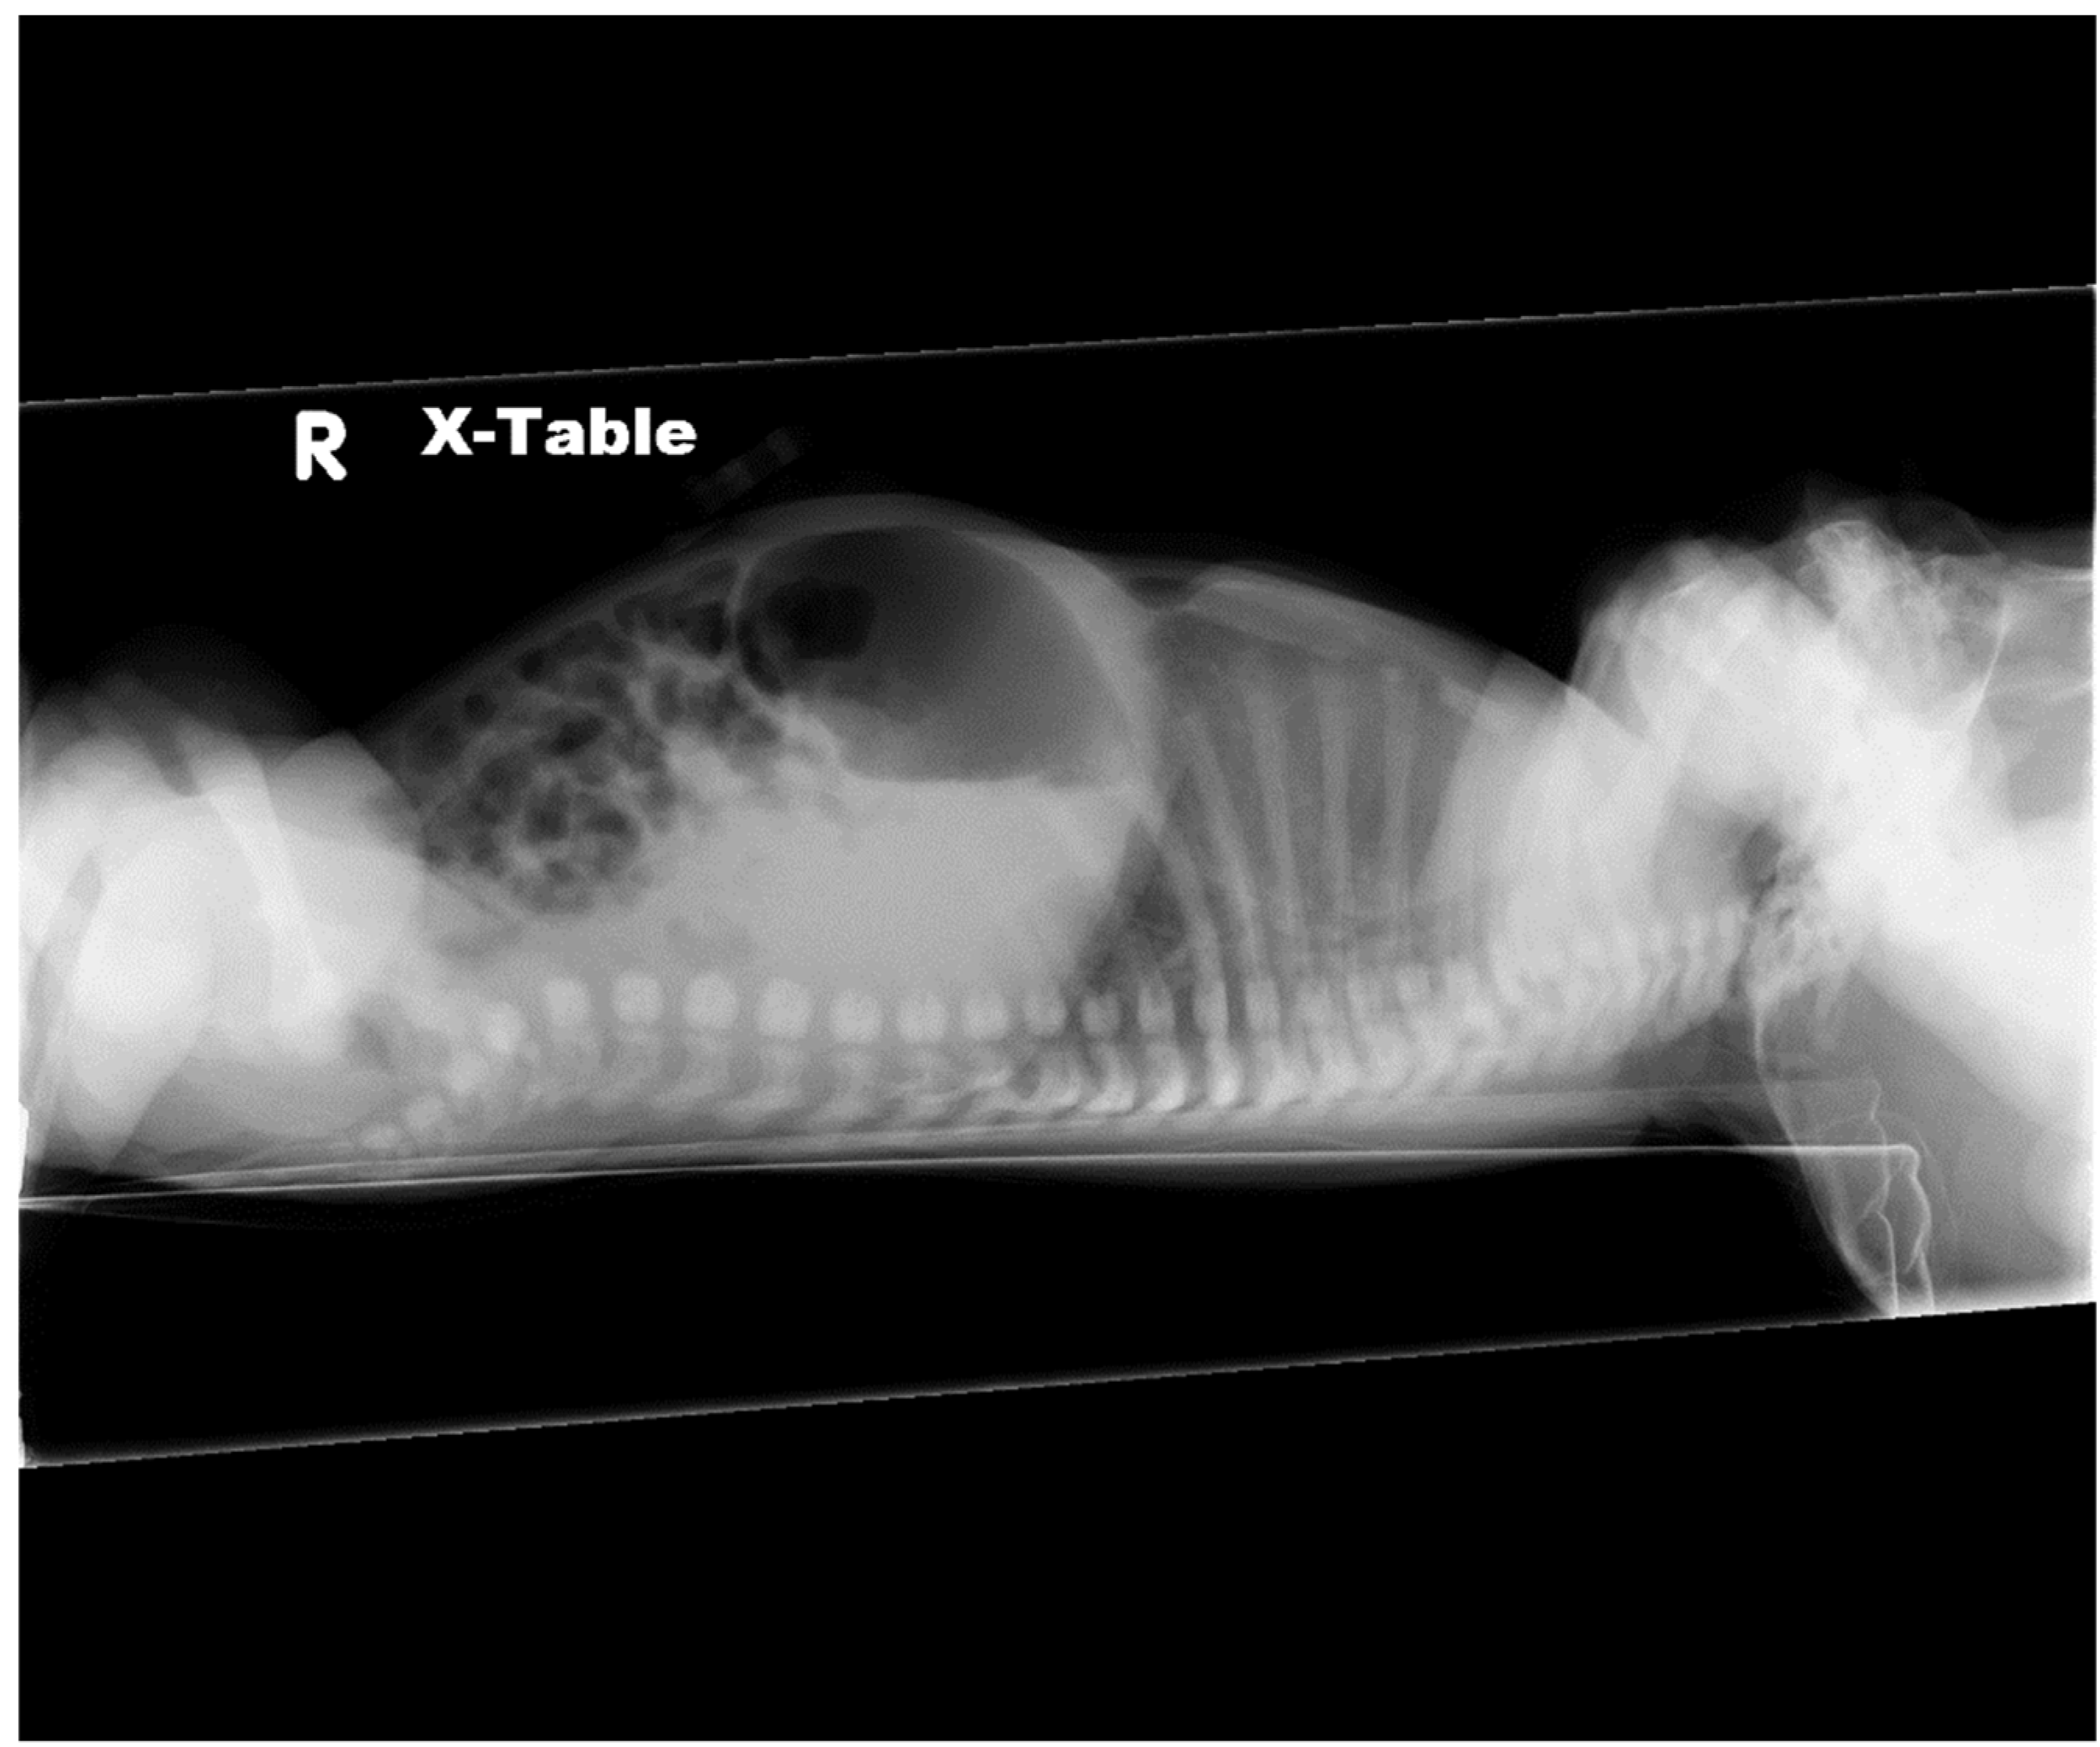

2.1. Case 1

2.2. Case 2